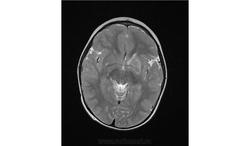

Помогите пожалуйста при постановке диагноза

Ребенок 2 года, заболели в середине декабре, гемипорез, к сожелению не могу ни как с контрасном исследованеим здесь загрузить но накапление контрасного вещества нет, спосибо за помочь!!!!!!!

Предположу гипоксически-ишемические изменения с диапедезным кровоизлиянием. Но они чаще двусторонние.